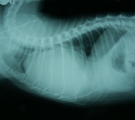

初診時胸部X線所見。心陰影拡大とスリガラス陰影あり。 第8病日さらに心陰影拡大し、心嚢液貯留が疑われた。 同日血膿様液を154ml抜去し、Pasteurella属を検出した。 退院2ヶ月後の胸部X線所見。心陰影正常で再発していない。

経過:初診時、体温:39.1℃ 心拍数:200/分 呼吸数:68/分。可視粘膜色良好。食欲元気なし。咳なし。聴診にて心音遠く感じられた。心雑音なし。肺音粗励。胸部X線にて心陰影拡大、気管分岐部挙上、肺野スリガラス陰影が認められた。動脈血ガス分析にてpH7.416, Pco2 27.3 mmHg, Po2 96.4mmHgと肺機能は保たれていた。心嚢液貯留と心機能低下による間質性肺水腫を疑い、利尿剤投与を始めた。翌日、スリガラス影は消失した。第8病日、さらに心陰影が拡大していたので、全身麻酔下、気管内挿管下にて心嚢液の試験穿刺を行った。麻酔前のCBC生化学検査ではWBC 11000/μLで左方移動認めず、ALB2.2g/dlと低下していた。伏臥位にて、透視下に22G静脈留置針を用い右第6肋間を穿刺した。計154mlの血膿様液(Ht9%, WBC>99900/μL, TP5.0g/dl)が抜去された。上清は黄色透明で比重1.033、TP5.0と滲出性、沈渣細胞診にて多数の変性好中球がみられた。培養にてPasteurella属の細菌が検出され、ABPC, AMPC, CEZ, EM, GM,AMK, MINO, OFLX, ENX, FOMに感受性を示した。由来は不明だが、化膿性心嚢液が貯留していたことが判明した。入院管理となりABPC20mg/kgとGM5mg/kgの投与を開始した。第12病日再び19mlの血膿様液を抜去したが培養にて菌は検出されなかった。それ以降心嚢液の再貯留を認めなかった。第22病日経過良好のめ退院。自宅ではバイトリル錠25mgを毎日投与してもらった。その後1ヶ月ごとに3ヶ月間継続して胸部X線心陰影を経過観察したが、再発を認めなかった。